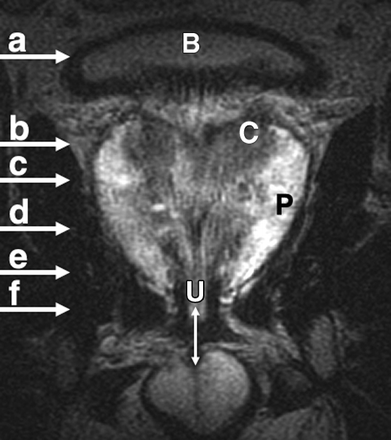

Most prostate cancers arise in the peripheral zone (PZ) [5], a region that may be compressed by the expanding transition zone (TZ) when there is significant BPH.

To improve PZ sampling it has been proposed that needle placement for systematic biopsies be directed more laterally [6], so that the biopsy tract traverses more of the PZ and encompasses the lateral PZ.

Although most prostate cancers originate in the PZ, up to 24% may arise in the transition zone (TZ) [5] and would therefore be missed by any biopsy protocol that sampled only the PZ.

Sextant biopsies were taken routinely ≈ 1 cm apart in the parasaggital plane bilaterally, at the base, mid-gland and apical regions of the prostate, as described by Hodge et al. [1]. In addition, six further biopsies were obtained, two from the TZ and four from the lateral PZ, as depicted in Fig. 1. The TZ biopsies were taken at the level of the mid-gland where the TZ was most prominent. The lateral PZ biopsies were taken by positioning the probe just medial to the lateral edge of the prostate at the base and mid-gland regions bilaterally, as described by Chang et al. [8]. This method generally allowed any area of DRE abnormality or suspicious hypoechoic lesion noted on TRUS to be incorporated into the biopsy protocol. All patients underwent the same biopsy strategy with no variance for gland size. Biopsies were obtained using an 18 G core-biopsy needle mounted on a spring-loaded automatic biopsy gun. All patients were placed in the left lateral decubitus ('knee-chest') position and all were examined with no prior bowel preparation. The procedure was generally well tolerated and no patient required intravenous sedation or narcotic analgesia. All TRUS was undertaken by the same operators (D.R.G. and N.S.), either personally, or when supervising a higher urological trainee.